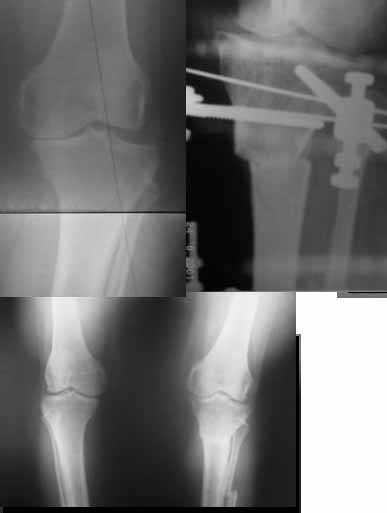

I do upper tibial osteotomies with either an ilizarov fixator and acute correction of the deformity or with an orthofix with gradual correction.

Sending you pics of the steps of the osteotomy and the frame.

You can do the osteotomy in a "focal dome" or in a transverse fashion. The dome has the advantage of having a good contact, allowing weight bearing as tolerated early on.

The level is below the tibial tuberosity.

The frame I use is pretty simple, with one wire each in the proximal and distal ring, two schanz pins in the proximal ring, and one each in the middle and distal ring.

I preconstruct a frame with the proximal ring in varus by the use of coupled washers in the threaded rods in the front and back. These are used as hinges, and after the correction, a medial and lateral threaded rod is also added.

Since the center of rotation of these deformities is usually near the knee joint line, lateral translation of the distal fragment is necessary to normalise all the axes.

You can also do the osteotomy in a transverse fashion.

When I use an orthofix fixator, the osteotomy is oblique, starting below the tuberosity and ending 1 cm away from the lateral cortex at the level of the head of the fibula. No fibular osteotomy is needed there. The deformity is gradually corrected over 2 or three weeks.

Very nice correction but, to my eye there is some 'over' correction of the tibia, now in some proximal valgus?